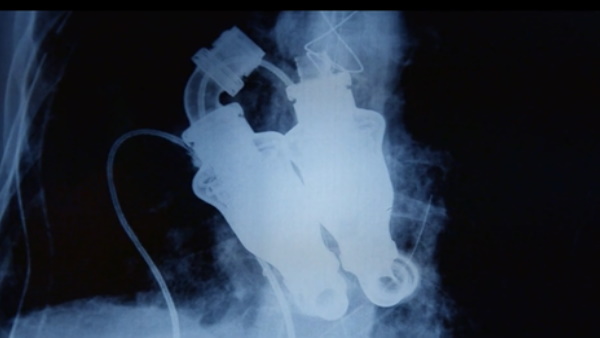

दरअसल, क्रेग लुईस जब दिल की बीमारी से लगभग मरने वाले ही थे उनकी मौत होने महज 12 घंटे शेष थे, तब उनकी पत्नी की परमीशन लेकर उनके दिल का ऑपरेशन करके उनके जिंदा रहते डॉक्टरों ने उनका दिल निकाल दिया और उसकी जगह "continuous flow," नाम की एक ऐसी मशीन लगाई जिससे क्रेग लुईस के शरीर में बिना पल्स के रक्त प्रवाहित होने में मदद मिली।

टेक्सास हार्ट इंस्टीट्यूट के डॉ बिली कोह्न और डॉ बड फ्रैजियर ने क्रेग को जिंदा रखने के लिए "continuous flow" डिवाइस को शरीर में लगाए जाने का प्रपोजल दिया, जो बिना पल्स के लुईस के रक्त प्रवाह में मदद करेगा जिसे उनकी पत्नी मान गई और क्रेग को नई जिंदगी मिली। चूंकि क्रेग लुईस के पास कुछ ही घंटे बचे थे, इसलिए उनकी पत्नी लिंडा ने डॉक्टरों को अपने पति के शरीर में डिवाइस लगाने की अनुमति दे दी।डिवाइस शरीर के माध्यम से रक्त के निरंतर प्रवाह की आपूर्ति करके इसे ट्रांसफर करने के लिए ब्लड का उपयोग करके काम करता है। डिवाइस स्थापित करने से पहले, लुईस को डायलिसिस मशीन, श्वास मशीन और बाहरी रक्त पंप पर रखा गया था।

टेक्सास हार्ट इंस्टीट्यूट के डॉ बिली कोह्न और डॉ बड फ्रैजियर ने क्रेग को जिंदा रखने के लिए "continuous flow," उपकरण को शरीर में लगाए जाने का प्रपोजल दिया, जो बिना पल्स के लुईस के रक्त प्रवाह में मदद करेगा जिसे उनकी पत्नी मान गई और क्रेग को नई जिंदगी मिली। दोनों डॉक्टरों ने मिलकर ये डिवाइस बनाई थी करीब 50 बछड़ों पर इसका परीक्षण किया था। उन्होंने जानवरों के दिलों को हटा दिया और उन्हें डिवाइस से बदल दिया। बछड़े अपने दैनिक कार्यों को करने में सक्षम थे- उनके शरीर में हृदय द्वारा रक्त पंप किए बिना। हालांकि इस उपकरण का उपायोग क्रेग से पहले किसी इंसान पर नहीं किया गया था।